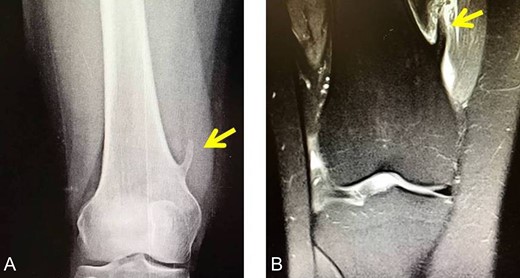

X-rays revealed an extra-articular mass at the medial aspect of the distal femur (Fig. 1A). Magnetic resonance imaging (MRI) confirmed the radiograph findings and no meniscal and ligament rupture or chondral defects were revealed. These characteristics were consistent with osteochondroma (Fig. 1B). Under general anesthesia, a standard antero-lateral portal used to access arthroscopically the knee. Cartilage surface, cruciate ligaments and menisci were normal. The osteochondroma was located extra-articularly, at the medial supracondylar side of the distal femur. Through a supero-medial portal and by perforating the capsule and a part of a medialis vastus muscle, the extra-articular lesion was reached arthroscopically (Fig. 2A). With an osteotome, the lesion was resected and removed with a grasper through the supero-medial portal (Fig. 2B). The remaining bony surface was abraded by a motorized shaver (Fig. 2C). The exostosis had maximum dimensions 3.1 × 2.5 cm. Histopathological examination confirmed the osteochondroma diagnosis.

(A) Arthroscopical view of the extra-articular knee osteochondroma, (B) Arthroscopic excision of the osteochondroma, C. Abrasion of the remaining bony surface.